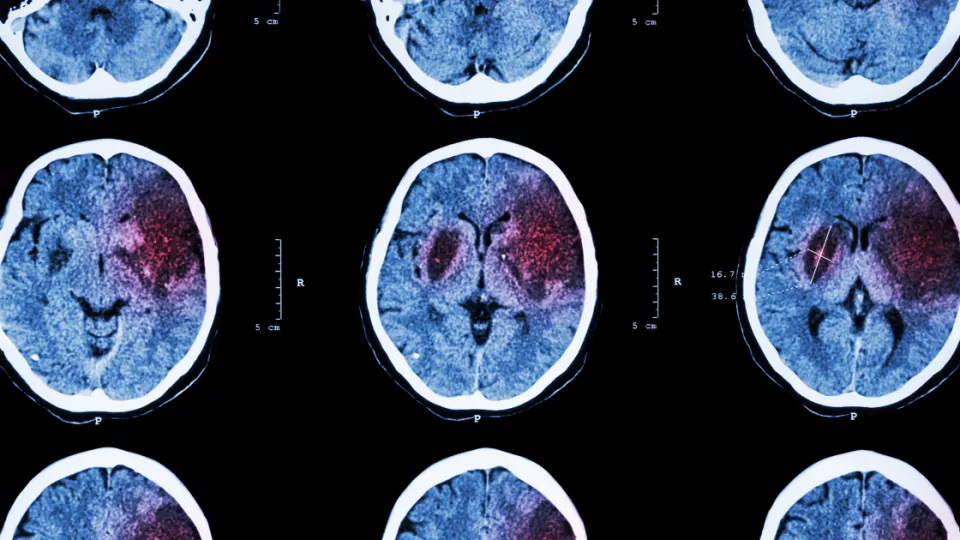

New Gene Variant Linked To Stroke

Researchers at Lund University in Sweden believe they have identified a gene variant that can cause cerebral small vessel disease and stroke

”The patients we have studied are from the same extended family, and several of them have been diagnosed with cerebral small vessel disease and suffered strokes. After tissue examination and using genetic sequencing methods, we found that they were carriers of a new gene variant that could be connected to their diagnoses,” says Andreea Ilinca, researcher at Lund University and neurologist at Skåne University Hospital.  Stroke is either caused by a blood clot that leads to a lack of oxygen in the brain, or a hemorrhage in the brain. High blood pressure, high cholesterol levels, diabetes, atrial fibrillation and lifestyle factors such as smoking are known risk factors for stroke. However, an increasing amount of research is indicating that genetic factors also play a major role.

Therefore, the Lund researchers have studied an extended family, the majority of whom live in southern Sweden, where eight out of 15 people developed cerebral small vessel disease. The disease is characterized by ischemic stroke (cerebral infarction caused by blood clots) and cerebral hemorrhage, as well as mild cognitive impairment, autonomic nervous system dysfunctions and coordination difficulties.

When examining tissue from those that had experienced symptoms, the researchers could see microscopic changes in the blood vessels of the brain and in small skin vessels.